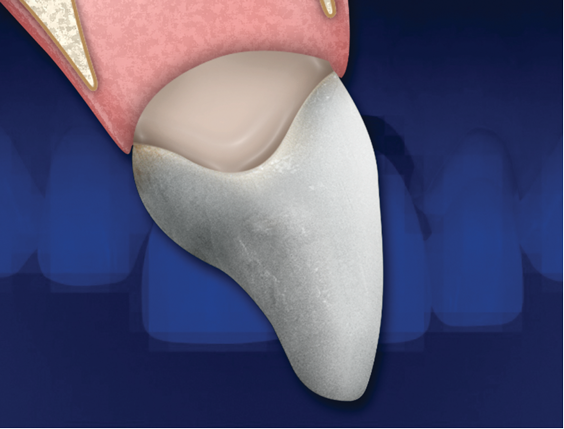

(2.) Ovate pontics should have a flat facial surface that goes approximately 1 mm under the gingival crest before it starts to become rounded. Wider ridges will accommodate more rounded ovate pontics.

Figure 2

It is essential that an ovate pontic be convex in all dimensions. However, with the traditional "egg in the nest" shape, the gingival marginal tissue over the facial aspect of the pontic is commonly rolled rather than knife edged, which can result in a shadow (Figure 1) and give away that it is a pontic rather than a natural tooth. Therefore, the critical issue isn't the shape of the intaglio surface of the pontic but rather the emergence profile of the pontic on its facial surface. Where the facial aspect of an ovate pontic emerges from the soft tissue, it should have the same contour as a natural tooth. Therefore, it should not be rounded. The facial aspect of an ovate pontic should have a flat surface that goes approximately 1.0 mm under the gingival crest before it starts to become rounded (Figure 2). The shape of the rounded surface of the pontic is determined by the thickness of the ridge in the created site. It will be more round for a thick ridge and more pointed for a thin ridge.